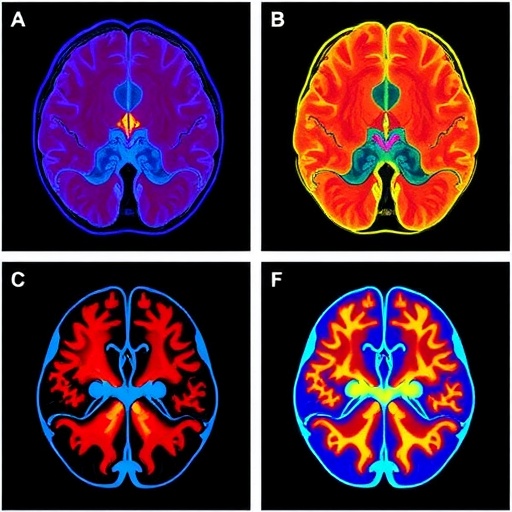

The practical utility of this approach was validated through in vivo experiments involving anesthetized mice prepared with cranial windows to expose the cortical vasculature. The team demonstrated that event cameras can capture vascular dynamics at an effective acquisition speed of 1000 Hz, a temporal scale previously unattainable without overwhelming data volume or sacrificing field of view. Widefield fluorescence images acquired using traditional sCMOS cameras provided a benchmark, while the event streams uncovered rich temporal information encoded in positive and negative brightness fluctuations induced by red blood cell passage through microvessels. This capability enables researchers to track rapid hemodynamic changes more precisely than before, opening new doors for the study of neurovascular coupling and cerebral blood flow regulation.

Beyond vascular imaging, the investigators extended their event-based framework to neuronal calcium activity monitoring, both in cultured neurons and in living mouse cortex. However, the inherently asynchronous, binary nature of event data posed analytical challenges, as neuroscientific paradigms typically rely on continuous fluorescence intensity traces expressed as ΔF/F₀. To surmount this obstacle, the team engineered an innovative self-supervised machine learning algorithm dubbed Implicit Neural Factorization (INF). This approach leverages the precise timing of event occurrences to infer continuous functional images from sparse event streams without the need for paired “ground truth” frames. INF reconstructs smooth and temporally resolved ΔF/F₀ images, facilitating direct comparisons with conventional imaging while retaining the data and speed advantages of event-based recording.